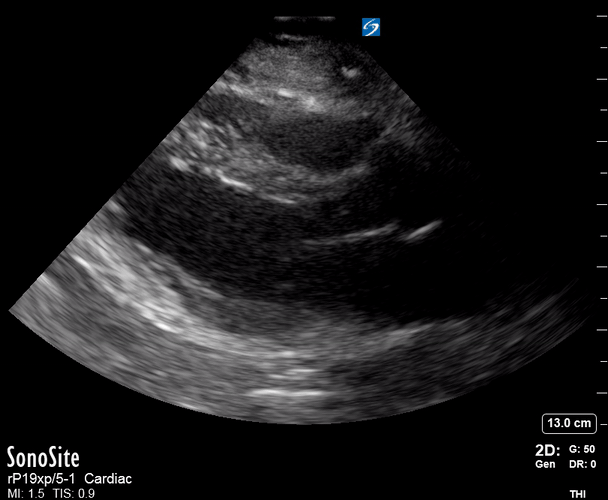

Exit: is there acute aortic root pathology?

Thoracic Aortic dissection is a time-dependent and deadly pathology that can occur silently or be masked by a variety of clinical presentations. While angio-CT remains the gold standard for diagnosis, US may be performed quicker and at the bedside. In the visible portion of the aortic root, the US findings can include intimal flap, aortic valve insufficiency, retrograde aortic flow, or rupture into the pericardium with pericardial effusion and tamponade. Alternatively, dilation of the aortic root is characteristic of a thoracic aortic aneurysm.

Importantly, remember that thoracic aortic dilation or intimal flap may occur distal to the aortic root, where an US scan is usually blind. Hence, the absence of dilation or flap does not rule out aortic disease.

THE VIEWS

The PLAX view is best for exploring the aortic root. If performed by an experienced operator, aortic root measurements in this window correlate well with angio-CT measurements.

The Aortic root size varies with age and gender and should be measured at its widest point, perpendicular to its long axis. In general, a root > 4 cm should be considered borderline and enough to warrant a formal study.

Alternatively, the aortic root size can be estimated by the rule of thirds, where in the PLAx view the size of the RV, AoR, and LA should be roughly 1:1:1.

AORTIC DISSECTION

In both of these views, US may detect an intimal flap seen as a hyperechoic linear structure within the aortic lumen that moves with each heartbeat. The visualization of a flap carries a high specificity and should prompt immediate consultation with cardiothoracic surgery; however, ultrasound sensitivity for intimal flap is significantly low, and its absence does not rule out aortic dissection.